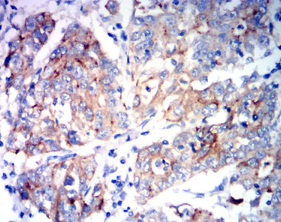

IHC    1/200 - 1/1000